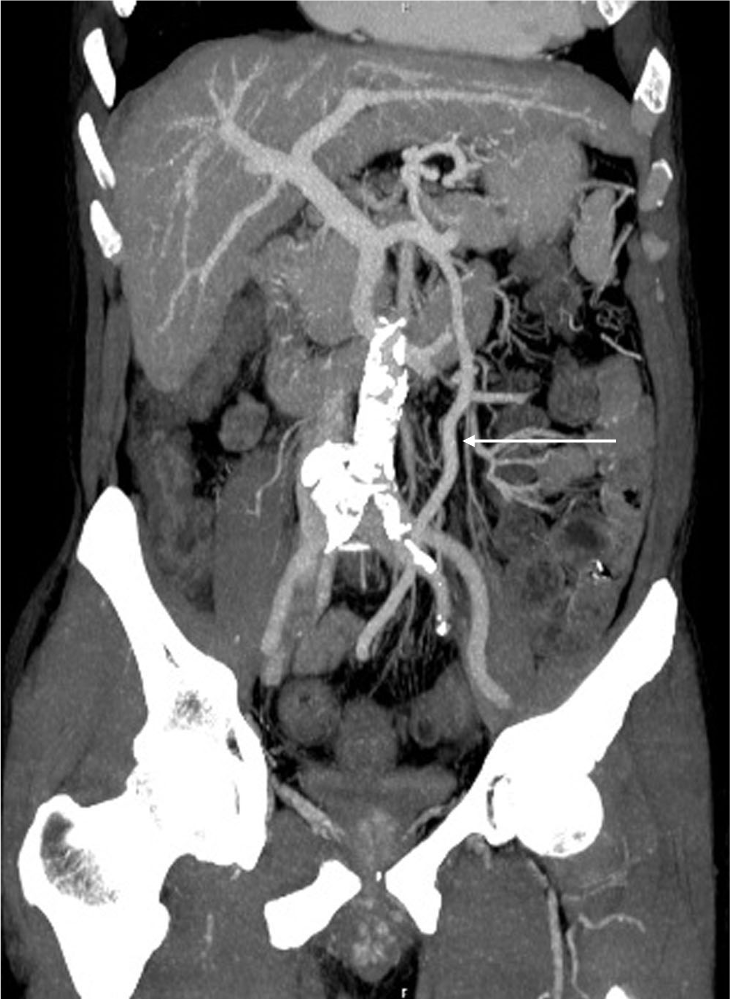

直腸静脈瘤の破裂予防目的にヒストアクリルを用いた経皮経肝的静脈瘤塞栓術を施行した。治療一か月後の治療効果判定に撮影を行った。

肝硬変のスクリーニング目的の造影CTにて直腸静脈瘤が判明した。破裂予防目的に経皮経肝的静脈瘤塞栓術を施行した。術前CTにて血管解剖を把握の上、治療を行った。術後一か月の造影CTにて、標的血管の良好な閉塞が確認された。

当該疾患の診断における造影CTの役割

直腸静脈瘤を始めとする異所性静脈瘤においては、IVR治療が選択されることが多い。術前に正確な解剖の把握が必要であり、造影CTの果たす役割は大きい。特に門脈系の良好な描出が求められ、適切な時相での撮影が肝要である。撮影後thin slice軸位断像での観察、任意多断面再構成像(MPR)やVolume rendering画像(VR)で評価を行い、術中のガイドとする。また肝細胞癌を併発することが多い為、動脈優位相における撮影も行う必要があり、dynamic studyを要する。治療においてはヒストアクリルや金属コイルなどのアーチファクト源となり得るデバイスが使用されるため、必要に応じてmetal artifact除去を活用する必要がある。また別部位に新たな静脈瘤が生じたり、腹水などの門脈圧上昇に伴う所見や門脈血栓などの合併症が生じる危険性があるため、造影CTによる評価が重要である。